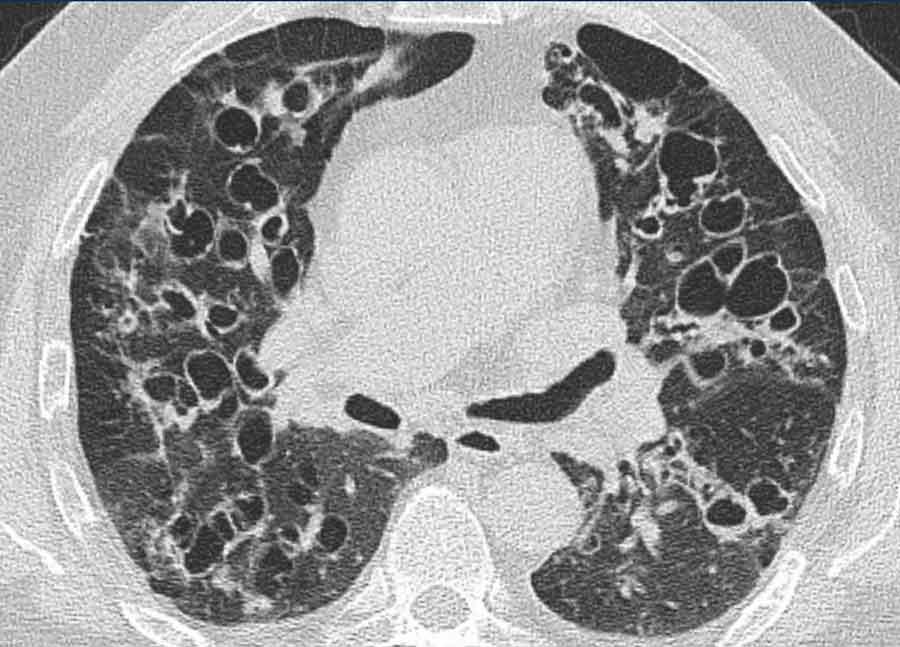

Hình ảnh cho thấy nhiều tổn thương dạng nang ở cả hai phổi (đầu mũi tên).

Trong một số ít trường hợp, tổn thương có thể lan rộng vào nhu mô phổi, biểu hiện là các nốt dạng nang thường gặp nhất ở các phân thùy đỉnh phụ thuộc trọng lực của thùy dưới. Có một nguy cơ nhỏ về biến đổi ác tính từ u nhú tế bào vảy thành ung thư biểu mô tế bào vảy.